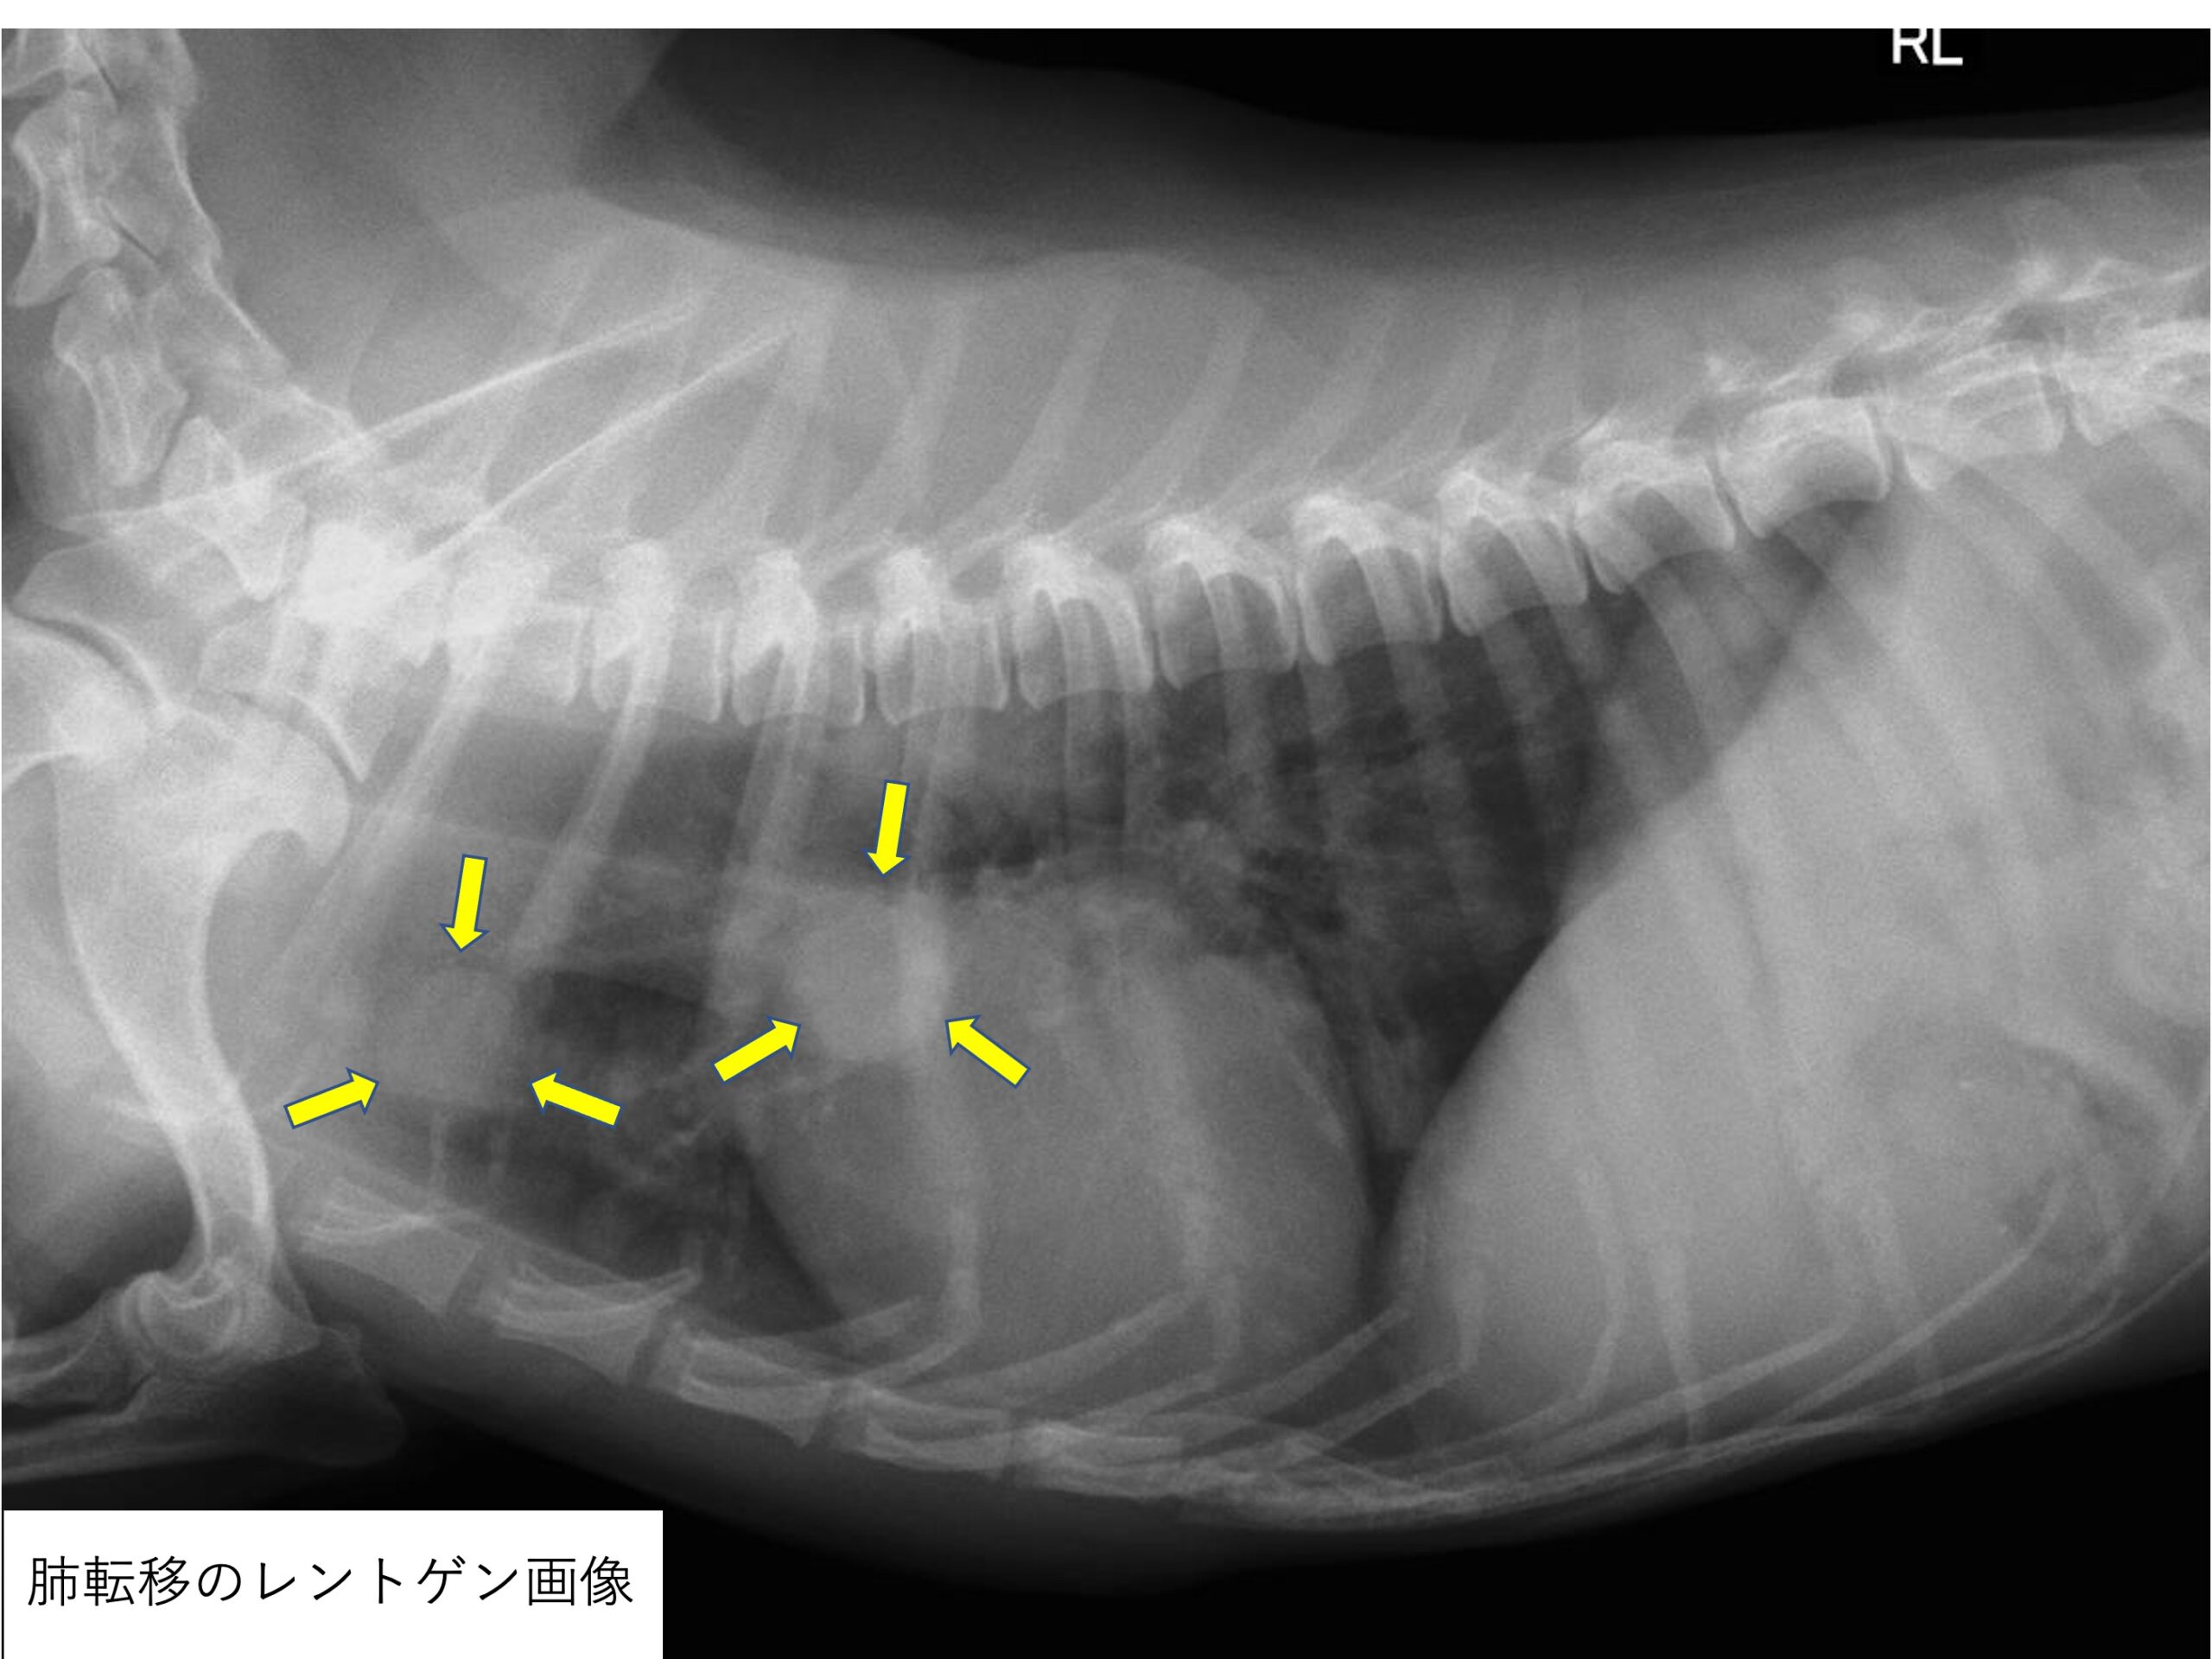

がんは甲状腺で発生しますが、がんが進行するにつれて、甲状腺から肺などの体の他の部分に広がる、つまり転移する可能性があります。肺で検出された場合でも、甲状腺がんの特徴があるため、依然として甲状腺がんと呼ばれます。

甲状腺がんの種類に応じて、肺転移の頻度は多かれ少なかれあります。たとえば、肺は甲状腺乳頭がんおよび濾胞がんの転移が最も多く見られる場所です。